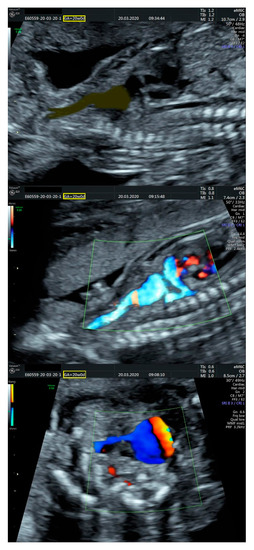

- an isolated aortic arch anomaly (supposedly aneurysmal dilation from which the left common carotid artery emerges) and coarctation of the aorta with the anterograde flow;

- ventricular septal defect, coarctation of the aorta, and a vascular formation located superior from the aortic arch with the appearance of an arteriovenous fistula;

- aneurysmal dilation located above the pulmonary trunk bifurcation and a dilated left common carotid artery with a retrograde flow;

- minor ventricular septal defect with a normal ductus venosus triphasic flow.